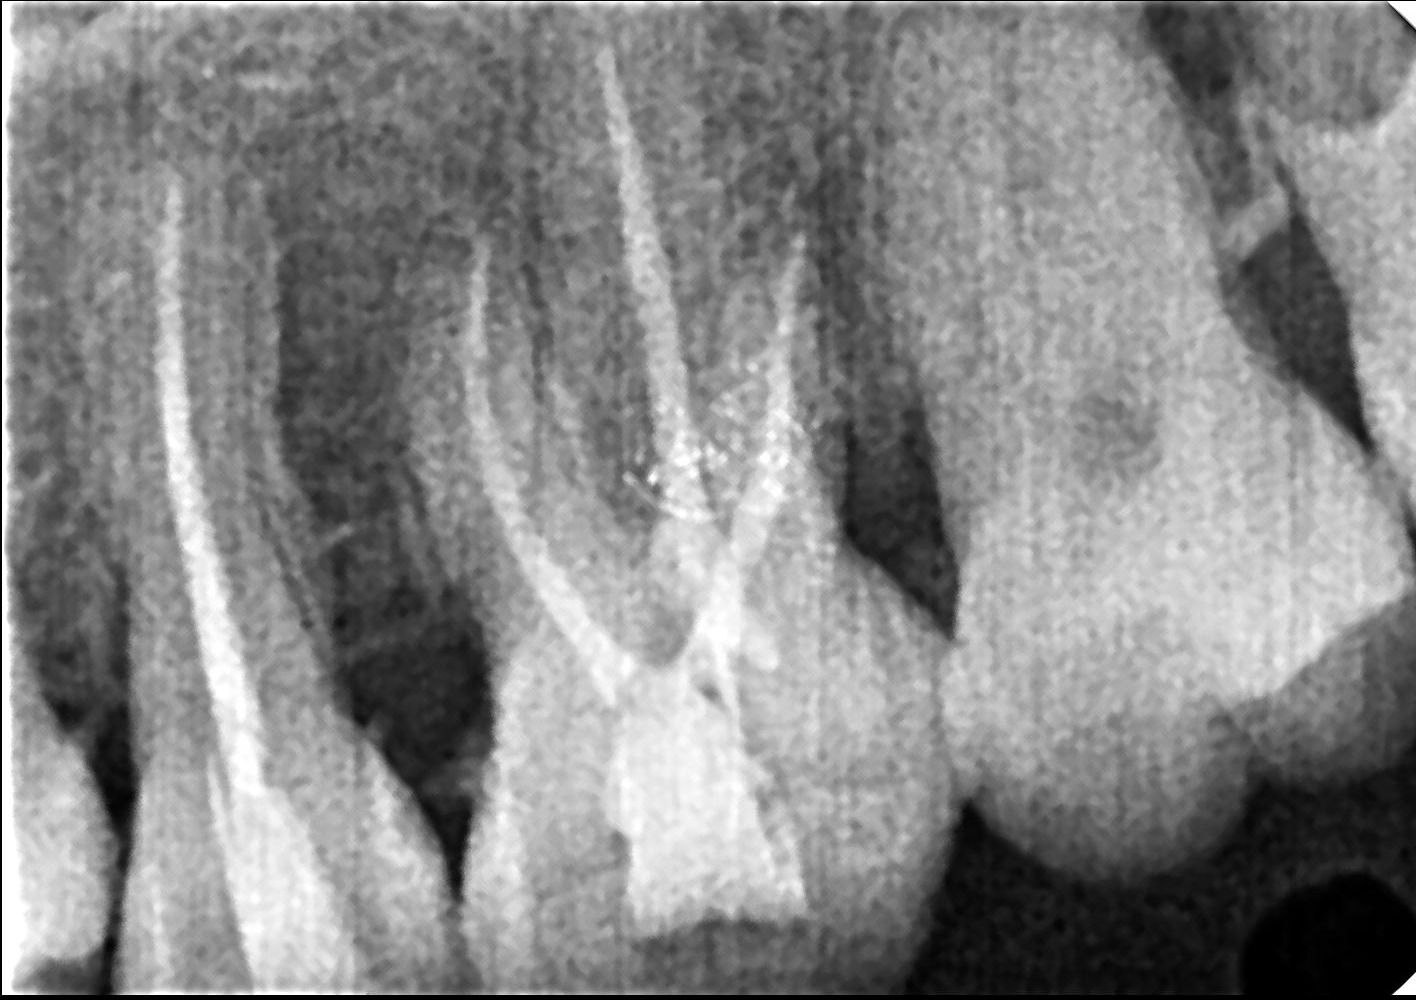

1. Consultation & Diagnosis

Time: 10–15 minutes

• Dental examination

• Digital X-ray to assess infection

At Procare Dental LLP, digital diagnostics help ensure accurate treatment planning.